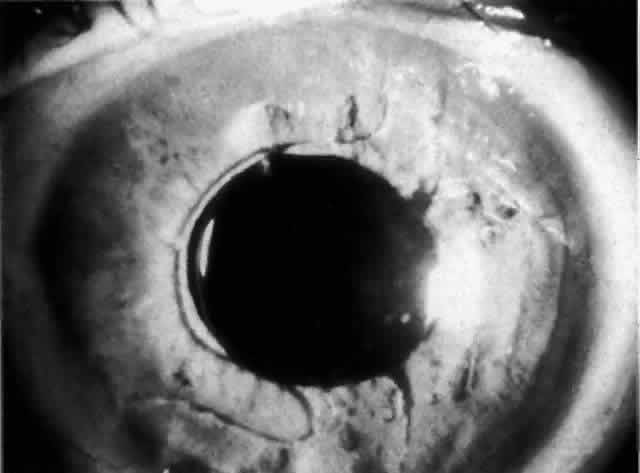

Cortical lens fragments retained in either the anterior chamber or the vitreous can also obstruct the trabecular meshwork in the form of free lens particles or macrophages swollen with lens material (Figs. 2 and 3). Glaucoma does not occur in all eyes that contain cortical remnants; the inflammatory response may be more pronounced and prolonged in eyes containing a higher amount of lens material. When inflammation is marked, keratic precipitates and sometimes a hypopyon may be present. Distinction between this sterile inflammatory endophthalmitis and infectious endophthalmitis can be difficult and may depend on the initial response to therapy. The presence or absence of IOP elevation is not helpful in making this distinction because IOP may be normal or elevated in both situations.